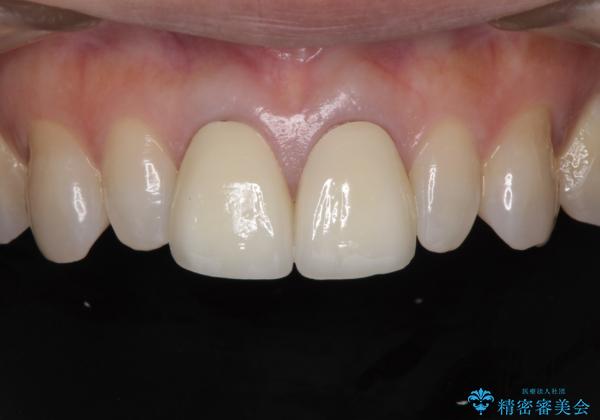

前歯をメタルフリーに 根管治療で不安を取り除いてから

セラミック治療と根管治療を行いました。

金属を使用したメタルボンドクラウンが入っていたため、いつかオールセラミックにしたいときに根管治療も行ったほうが良いとご提案し、今回行いました。

色について

歯と歯肉の境目の色は、歯自体が黒くなっている場合、完全にカバーすることは難しいです。